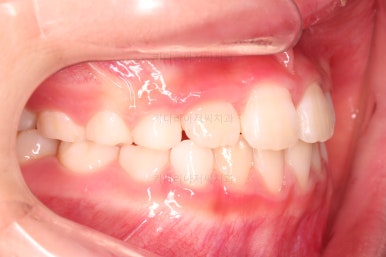

1. 초진

부산어린이교정 키다리아저씨치과에 처음 내원했을 당시의 입안의 모습입니다.

앞니가 거꾸로 물리는 전형적인 앵글씨 3급 부정교합 환아의 모습이었습니다.

아직 유치가 많이 남아 있었꼬, 아래 앞니는 4개가 영구치 맹출, 윗니는 2개가 영구치 맹출 상태였습니다.